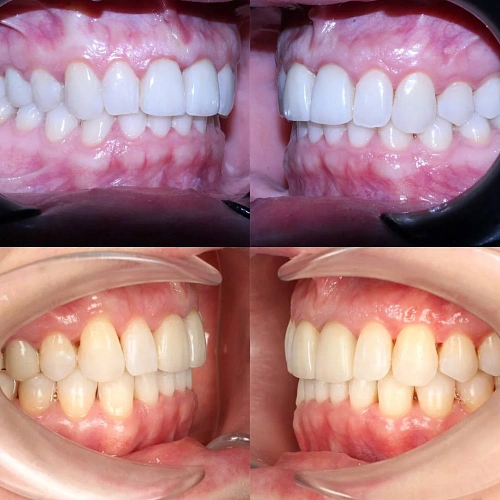

Диагностика

Верхняя челюсть выступала вперёд относительно нижней с обеих сторон (II класс по Энглю). Обе челюсти сужены, зубы стояли скученно. Нарушена кривая смыкания — жевательные зубы были на разной высоте. На двух передних зубах верхней челюсти ранее установлены металлокерамические коронки.

Прозрачные элайнеры Click на обе челюсти. Расширить зубные дуги, убрать скученность, исправить прикус и выровнять линию смыкания. Лечение с учётом имеющихся коронок. Основной набор — 31 капа. Срок — около 1,5 лет.

Лечение заняло 20 месяцев (июнь 2024 — февраль 2026). Понадобились два дополнительных набора: 26 и 7 кап — итого 64 капы. Несмотря на дозаказы, лечение уложилось в нормальный срок.

Результат

Зубы выровнены, скученность устранена, прикус исправлен, линия смыкания нормализована. Ретейнер установлен на нижнюю челюсть. На верхней ретейнер не ставили — на передних зубах коронки, вместо этого изготовлены ретенционные капы на обе челюсти. Пациентка направлена к ортопеду для замены коронок.

Проблема: Пациентку беспокоили неровные зубы и неправильный прикус. При осмотре нашли сразу несколько проблем: обе челюсти сужены, зубы стоят скученно, верхняя челюсть выступает вперёд (II класс по Энглю), кривая смыкания деформирована — жевательные зубы на разной высоте. На двух передних зубах верхней челюсти стояли старые металлокерамические коронки, которые нужно было учитывать при планировании.

Решение: Поставили элайнеры Click на обе челюсти. Основной набор — 31 капа, плюс два дозаказа: 26 и 7 кап, итого 64. При этом лечение уложилось в 20 месяцев — быстро для такого объёма работы. Расширили дуги, убрали скученность, исправили прикус, выровняли линию смыкания. Ретейнер поставили только на нижнюю челюсть. На верхней от ретейнера отказались сознательно — на передних зубах коронки, и проволока там не ляжет корректно. Вместо этого изготовили ретенционные капы на обе челюсти. Ортопедию — замену старых коронок — пациентка будет проходить у себя в городе.

Непростой случай: II класс, сужение, скученность, деформация кривой Шпее и металлокерамические коронки на 11 и 21. Коронки ограничивают варианты ретенции — на верхней челюсти вместо ретейнера используем капы. Это осознанное решение, принятое совместно с пациенткой. 64 капы за 20 месяцев — хороший темп для такого объёма. Основной набор сделал базу, дозаказы довели до нормы.